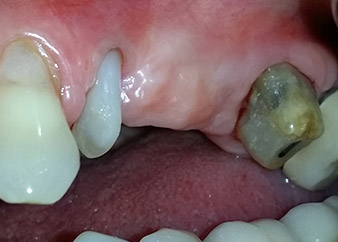

Risultati intermedi dopo due mesi

Le figure 17 e 18 mostrano il risultato clinico due mesi dopo l'intervento chirurgico. Il dente 24 mostra mobilità ridotta di classe 1 secondo Miller e i tessuti molli sono privi di infiammazione. A questo punto l'utilizzo della sonda è stato evitato per impedire una nuova infezione e per non disturbare l'attacco epiteliale. Era stata programmata una visita di controllo al rientro e il posizionamento dei perni di guarigione sei mesi dopo l'inserimento degli impianti.

Due mesi dopo l'intervento chirurgico il paziente non lamentava dolore.

Fig. 17: Due mesi dopo l'intervento chirurgico, il paziente non lamentava dolore e l'area non presentava infiammazione.

dopo l'intervento chirurgico

Fig. 18: Il dente 24 ora mostrava minore mobilità.

Durante la visita prevista due mesi dopo l'intervento chirurgico, la mobilità del restante "elemento dentale" 24 si era già ridotta dalla classe 2 secondo Miller alla classe 1. L'attacco del tessuto molle era a livello del vicino dente 23. Inoltre, la paziente non presentava sintomi endodontici o periodontali, quindi la prognosi è stata rivista.

Tuttavia, poiché la maggior parte del tessuto osseo buccale e prossimale è mancante e il materiale composito di ricostruzione si estende fino alla sezione apicale della radice, per ragioni biologiche non è possibile attendersi un livello di riattacco più elevato (Sculean et al., 2008).